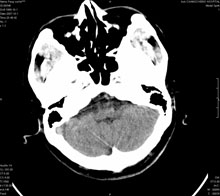

男,41岁,间断抽搐1小时,失神5分钟,bp130/90mmhg。低密度区ct值约16hu。

脑实质见多发散在的钙化点,左顶叶见一囊变灶,多考虑脑囊虫。

多发的囊泡(多发囊型)+多发的钙化(慢性钙化型)=混合型

典型的脑囊虫病。

典型脑囊虫病